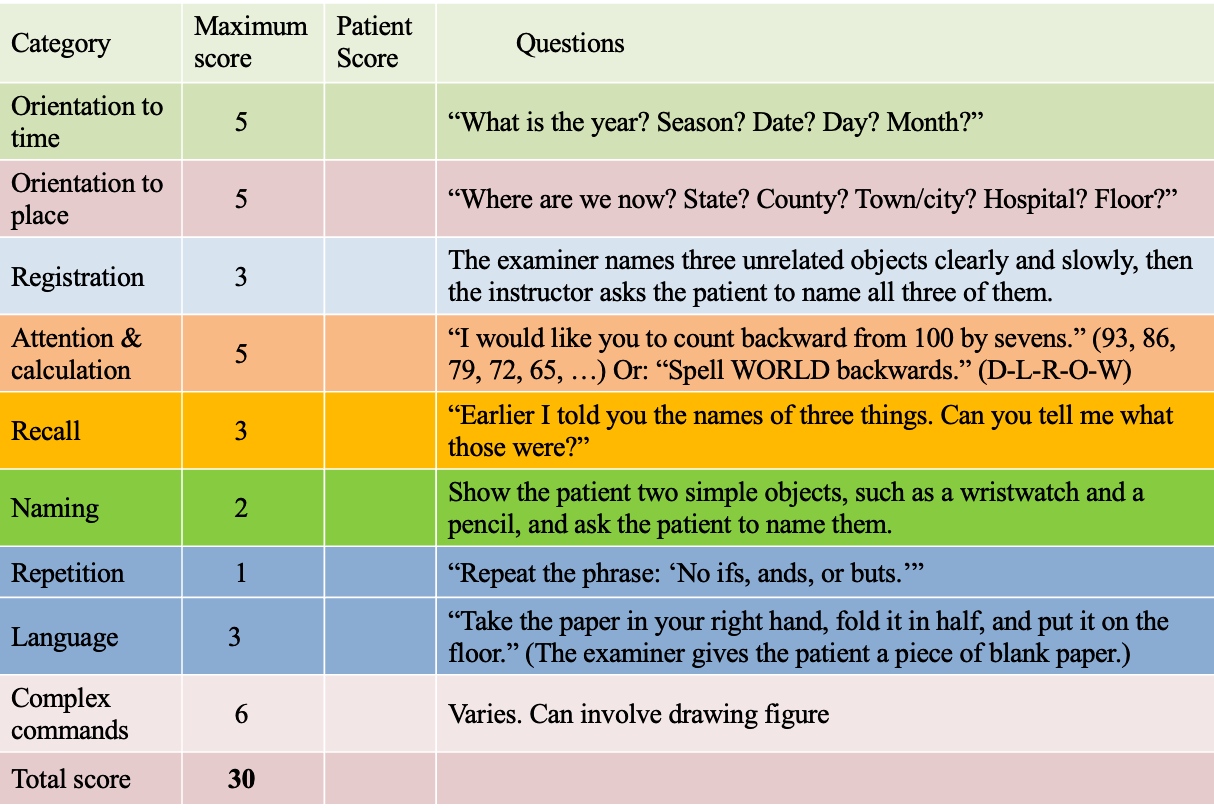

Scores

A) Mini–mental state examination